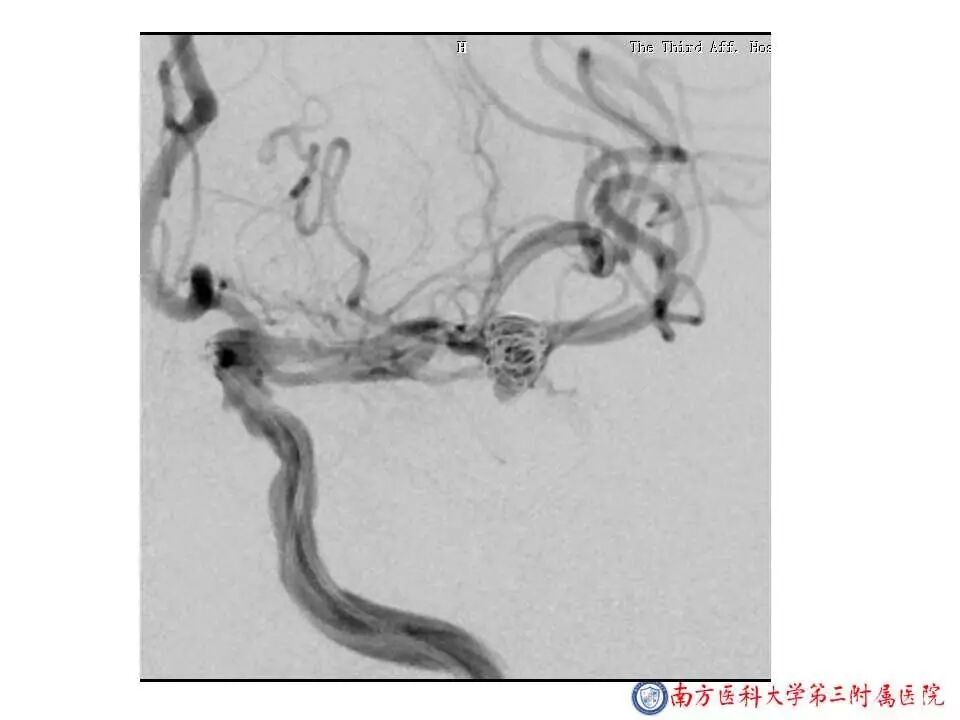

今天为大家分享的是“强生医疗CNV-神经介入专栏”第二十五期,由南方医科大学第三附属医院神经外科主任黄理金教授带来的“Enterprise支架辅助栓塞动脉瘤的优势”精彩讲课视频及PPT,欢迎观看。文章仅代表作者个人观点,如有不同见解,欢迎同道斧正!